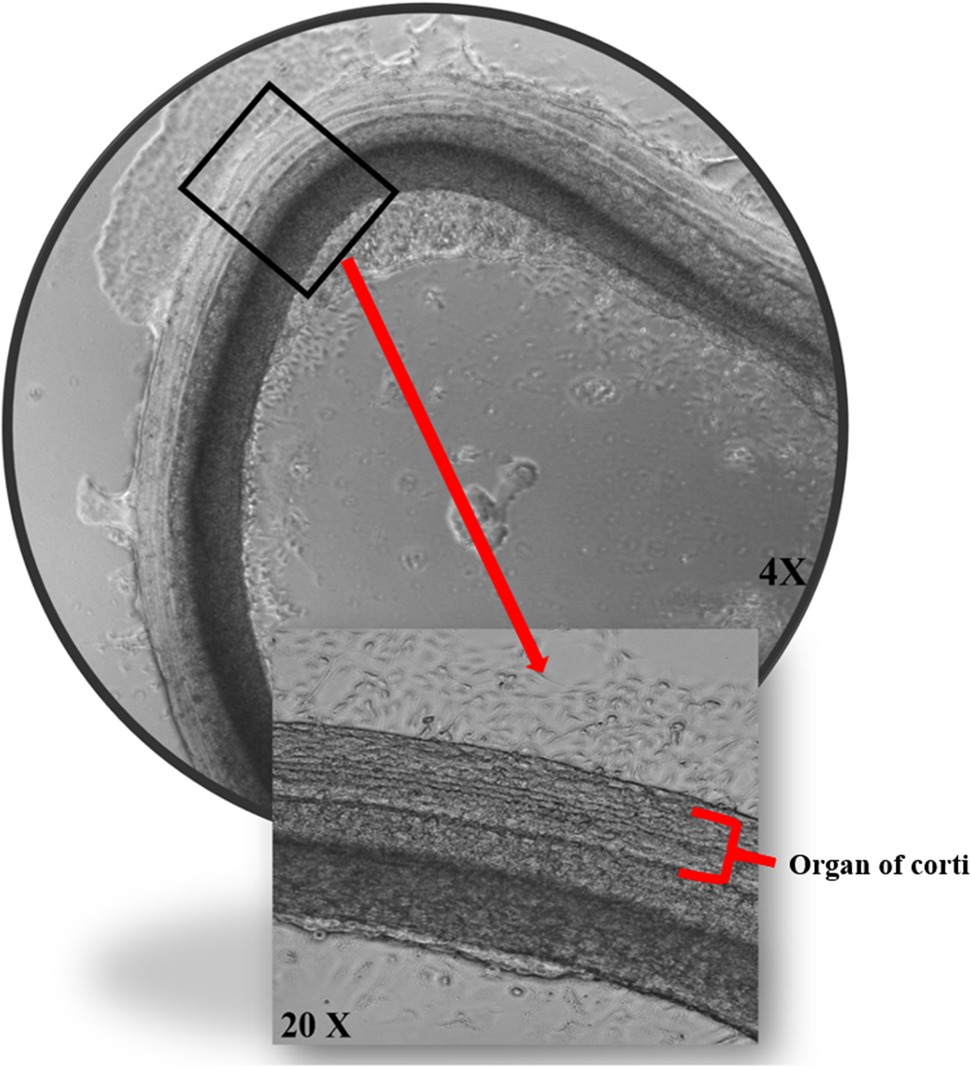

As per the American Veterinary Medical Association (AVMA) guidelines, decapitation of pups (P0–P2) was quickly performed using sharp surgical scissors (28). The decapitation procedure was performed according to the animal care standardized practice. Dissection protocol of CD-1 pups’ inner ear was performed as described in detail by Meas et al. and Ogier et al. with some modifications. After decapitation, the heads were dropped into ice-cold HBSS with 1% HEPES on a dissecting plate to separate the organ of Corti. The bony cochlear wall was gently removed, then the spiral ligament/stria vascularis unwound from the modiolus, and the dissected cochleae were finally transferred to a Matrigel-coated plate, ensuring the correct orientation with the organ of Corti facing upward. After the inner ear explants underwent overnight incubation for optimal adhesion, the media were changed the following day (27, 29).

Figure 2. The effects of porphysomes on cochlear explants. Cochlear explants from our work under transmitted light microscopy posttreatment with ePS showing intact three outer rows and one inner row of hair cells.